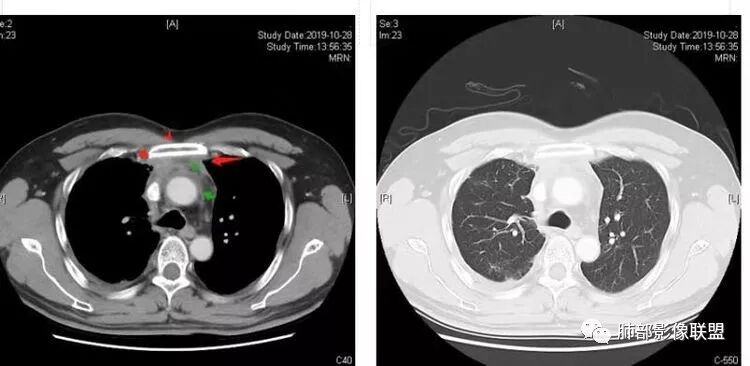

穿越七海的风:右前纵隔占位,恶性肿瘤,生殖来源?右肺实变是占位or肺不张?考虑为部分肺不张FeNo:右前纵隔占位,右肺结节,胸膜凹陷,小尾巴,右肺不张,考虑恶性杨旭华:恶性,前纵隔肿物,与血管关系密切,上腔静脉变窄,右肺野一元论考虑叶间裂增厚,恶性胸膜间皮瘤可能大小丽:到底是纵隔来源还是胸膜来源?我怎么倾向于胸膜来源,和叶间胸膜关系密切,而且纵隔内上腔静脉是向内侧推移。胸膜肿瘤(间皮瘤?SFT?)包裹性胸腔积液?马春平(张家港市一院胸外科):前纵隔占位,左无名受压,右大量胸腔积液可能是胸导管汇入处侵犯受压,考虑纵隔鳞癌孙冰伟:右上纵隔占位,也感觉和叶间胸膜关系密切,右侧胸膜局限性增厚,考虑恶性可能性大灵:前纵隔占位,血性胸水,胸膜凹凸不平,查见肿瘤细胞,结合免疫组化考虑胸腺癌。鉴别胸膜间皮瘤。采莲:右前上纵膈旁可见类圆形肿块,纵隔血管内移,感觉来源于胸膜,肿块内密度低,似水样密度,右侧胸膜广泛增厚,少量胸腔积液。心包少量积液。考虑胸膜间皮瘤,鉴别肺癌并胸膜转移?水晶石头:患者中年男性,胸闷15天。有“高血压、慢性肾小球肾炎”病史。查肿瘤标志物正常,胸水提示渗出液,胸水病理查见瘤细胞。胸部CT:右肺上叶后段结节、斑片影,见胸膜牵拉、包裹积液及部分纤维条索灶,似见卫星灶,右侧胸膜增厚。前纵隔脂肪密度增厚,右侧可见类圆形低密度(液体)肿块,边缘光滑。综合考虑右肺腺癌并胸膜转移,结核可能。周太狼:考虑纵隔胸膜来源肿瘤,恶性,胸膜间皮瘤伴转移?徐飞:中年男性,影像为右侧胸腔及叶间积液,叶间胸膜增厚轻度强化。前纵隔右侧心缘旁团块,可见坏死。胸水见癌细胞,综合考虑恶性,胸腺癌伴转移。小赵:中年男性,血性胸水,常规查见癌细胞,李凡他实验阳性。胸部CT示前纵隔见不均匀密度影,与邻近大血管分界不清,囊变坏死明显,增强扫描呈不均匀强化,心包及右侧胸膜增厚,并心包及右侧胸腔少量积液。综合考虑胸腺癌。右肺中叶病变周围见多发纤维条索,支气管部分进入病灶,考虑炎性病变。流心明智:患者,男性,50岁。胸闷15天。高血压20年,慢性肾小球肾炎15年。肿标正常,胸水提示渗出液,胸水查见癌细胞。胸部CT:右肺肿块影,斑片影,索条影,可见胸膜牵拉、多发包裹积液,纵隔上腔静脉受累,心包受累。综合考虑:ROSE似腺?考虑右肺腺癌并胸膜转移,心包受累。鉴别胸腺Ca、淋巴瘤,纵隔病变不懂,等老师们精彩分析。王秀仙:前纵膈囊实性肿块,与纵膈分界不清,心脏大血管及上腔静脉受压向内后移,右侧后胸膜、侧胸膜增厚,右侧叶间裂不规则增厚,心包积液,根据腔静脉移位情况,考虑纵膈胸膜来源恶性肿瘤,胸膜间皮瘤?鉴别胸腺癌并胸膜转移。高广飞:上纵隔占位,右侧叶间胸腔积液,需考虑恶性自信人生:多发囊实性病灶,包裹性积液,考虑胸膜来源 只是没有看到壁结节,恶性胸膜间皮瘤巴伟:前上纵隔占位,胸膜及心包结节,考虑胸腺瘤或癌,右肺病灶,先考虑陈旧炎性病变。Lenle董:前纵隔占位,部分边缘模糊,病灶内囊变?坏死?上腔静脉受侵,考虑胸腺癌;叶间片状影,强化明显,炎性考虑。常志强:前纵隔囊实混杂密度肿块,边界不清,实性部分强化明显,结合胸水内见癌细胞,考虑恶性肿瘤伴转移。飞鹰行动:前纵隔占位,软组织密度及囊性密度,实性部分密度均匀,致密,病灶与周围血管分界不清,增强后病灶强化有类似不温不火强化,部分血管受侵犯,右肺见肿块样病变及条索状病变,一元论,考虑淋巴瘤,二元论,考虑胸腺瘤B2—B3伴右肺病变。尽量一元论考虑,淋巴瘤可能。看图说话:右肺索条病灶,边缘膨隆,胸膜牵拉,考虑右肺癌伴胸膜转移。晨:前纵隔囊实性肿块,与纵隔分界不清,右侧后胸膜、侧胸膜增厚,右侧叶间裂不规则增厚,考虑纵隔胸膜来源恶性肿瘤,考虑胸腺癌并胸膜转移。丽:中年男性,前纵隔囊实性肿块,呈偏心性生长,临近大血管受压推移,增强后实性部分不均匀强化,心包可见条形积液,考虑胸膜来源恶性肿瘤,胸腺癌可能大。另右肺多发斑片状高密度影及实变密度影,实变影呈均匀强化,右侧胸膜局限性增厚,考虑炎性病变。小飞:右前纵隔囊实性占位,实性部分明显强化,右侧叶间胸膜增厚,右侧胸腔积液,心包积液,考虑恶性胸腺瘤!尘缘:支持恶性胸腺瘤(囊实性肿块,实性强化,且侵犯纵隔,脂肪间隙模糊)伴肺内及胸膜转移。浪迹天涯:考虑侵袭性胸腺瘤——胸腺前纵隔占位,周围脂肪间隙模糊不清。尘缘:不除外另一种可能:二元,肺内腺癌合并胸膜转移,纵隔的畸胎瘤可能。一米阳光:晨读中年男性,右肺结节影,叶间裂及胸膜增厚牵拉,右侧胸水。心包多发结节改变。胸水查见癌细胞。考虑,腺癌并转移。鉴别,胸膜间皮瘤并转移前纵隔囊实性占位,二元考虑。心灵鸡汤:老年男性,右肺中叶外段长条状软组织密度影,边缘膨隆,邻近胸膜牵拉,部分胸膜有栽脏,右中叶外侧段支气管堵塞,常规考虑恶性肿瘤,腺癌可能,结核、鳞癌不除外,另右肺上叶斑片影,小叶性肺不张?右前纵隔囊实性不规则形密度影,其内见部分脂肪样极低密度影,与邻近血管边界不清,心包外膜有侵犯,增强未见纵隔窗平扫,实性及分隔见增化,其内低密度影未强化,考虑低度恶性纵隔肿瘤,间皮瘤可能,畸胎瘤、淋巴瘤待排,建议支气管镜及穿刺活检。曹志勇:右前纵隔考虑来源于胸膜的恶性肿瘤,右肺内病灶考虑鳞癌,二元德芙~云味:中年男性,右肺见结节、斑片影,右侧包裹积液、胸膜牵拉,纤维条索,前纵隔囊性占位,考虑腺癌、并转移。欧阳英:右前中纵隔囊实性肿块及右肺内结节灶,支持恶性肿瘤,胸腺癌并肺内转移可能张延军:前纵隔见不规则软组织影,密度不均,右侧缘见囊变区,纵膈及侧胸壁胸膜增厚,增强呈不均匀强化,右肺中叶见结节灶,近段支气管阻塞,叶间胸膜不规则增厚,考虑1:右肺中叶腺癌伴纵膈及胸膜转移;2:前纵膈侵袭性胸腺瘤并胸膜侵犯,中叶炎性改变?彭君:老年,前纵隔占位 ,坏死边缘清, 侵犯心包 右侧胸膜及叶间胸膜结节 ,少量胸水, cea不高 ,考虑恶性, 间皮瘤可能 ,转移待除外。毛勤香:恶性没问题,胸水查见癌细胞,一元还是2元,右肺中叶肿块,边缘毛糙,局部似有毛刺,周围有粘连,右侧胸膜腔少量积液,胸膜增厚多发结节,含叶间裂结节,纵膈脂肪间隙模糊,纵膈胸膜增厚,心包增厚积液,右前那个类圆形低密度肿块,纵膈血管内移,我考虑胸膜来源可能性大,综合考虑,一元肺腺癌并多发转移,二元考虑胸膜间皮瘤并多发转移,肺内炎症不张。

南边:大家看看前纵隔的病灶,符合肿瘤吗脂肪,周围密度增高

三个石头:比较散;像炎症的蔓延生长南边:是,这些看着心里不踏实觉得把这个纳入肿瘤去考虑是否合适总觉得边缘收缩的、散在的朝周围蔓延;中央还跨过脂肪,朝对侧胸膜蔓延把这个与囊性病变连到一起去考虑是否还需要斟酌一下因为这个就方向差异大了南边:连在一起,囊实性,边界不清,自然考虑恶性:如果独立,囊张力高、边界清楚,间隔,自然朝良性考虑:

Coke with ice:囊性部分考虑包裹性积液?南边:不是积液;有间隔;张力高;而且位置有些特殊

大家仔细看看积液中的游离气体;

不是支气管,是积气;是穿刺进去的;

囊内密度不一致

我认为囊张力高,积液中的气体均在周围,外侧、下方,囊内有间隔:各腔密度不一致;提示:囊腔属于前纵隔,不是包裹性积液;现在的问题:囊腔与内侧的病灶是否是一体的

南边:我总觉得这个纵隔内不像是一个肿块的改变,扁平,周围蔓延:有符合炎性的的特点,或者肿瘤的侵犯;但是肿瘤的侵犯,不大符合,实性部位的边缘过于柔和,没有毛糙的侵犯边缘。

本例纵隔与肺内两处病变,回顾总结分析:

2、前纵隔内病灶囊实性混杂密度病灶,囊性病灶主要位于右侧,张力较高,有分隔影,囊壁右侧缘光整,病灶左侧实性部分边界不清明显强化,病灶肺瘤交界面大部分边界清楚,部分模糊。

前纵隔肿块伴囊变坏死常见以有胸腺瘤、胸腺癌、淋巴瘤和生殖细胞肿瘤。

胸腺瘤/胸腺癌:病灶内那么大的囊,常规考虑B型以上胸腺瘤,囊内有分隔影,病灶周围脂肪间隙模糊,常规考虑侵袭性胸腺瘤或胸腺癌,若侵袭性胸腺瘤,常侵犯胸膜、心包,很少累及肺。胸腺癌易侵犯胸膜、肺并纵隔淋巴结及远处转移。但肺内腺癌形态更符合原发灶。胸膜及叶间裂转移则即可来自肺,也可来自胸腺癌。